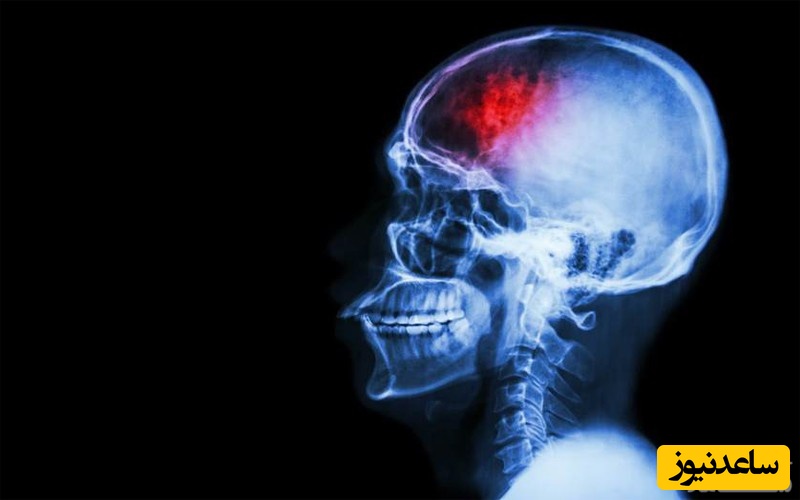

ضربه مغزی نوعی آسیب به مغز به شمار می رود که منجر به از دست دادن موقت عملکرد طبیعی مغز می گردد. این شرایط از نظر پزشکی، به عنوان یک سندرم بالینی تعریف می شود که با تغییر فوری و گذرا در عملکرد مغز، از جمله تغییر وضعیت ذهنی یا سطح هوشیاری ایجاد شده در نتیجه نیروی مکانیکی یا ضربه، مشخص می شود.جمجمه از مغز در برابر ضربه و برخورد با اجسام تیز محافظت می کند، اما تمام تاثیر یک نیروی سخت را جذب نمی کند. مغز در داخل جمجمه توسط مایع مغزی نخاعی اطراف آن محافظت می شود. با وجود این، یک ضربه ناگهانی به سر، یا حتی کاهش سرعت به صورت کاملا سریع، می تواند باعث تماس مغز با قسمت داخلی جمجمه شود. بدین ترتیب احتمال پارگی رگ های خونی، کشیدن رشته های عصبی و کبودی مغز نیز وجود دارد.

ضربه مغزی می تواند در اثر ضربه مستقیم به سر، مانند سقوط، ضربه خوردن یا ضربه مغزی در اثر تصادف ایجاد شود. این وضعیت همچنین قادر است در نتیجه سرعت بالا و توقف ناگهانی سر، مانند جراحات ضربه ای با سرعت بالا یا آسیب ناشی از انفجار، مانند یک منطقه جنگی، رخ دهد. بسیاری از افراد تصور می کنند که ضربه مغزی شامل غش کردن یا از دست دادن هوشیاری است، اما این تفکر درستی نیست. در بسیاری از موارد، افراد مبتلا به ضربه مغزی هرگز هوشیاری خود را از دست نمی دهند. در چند مورد، علائم خارجی ضربه به سر، مانند خونریزی، نیز ممکن است وجود نداشته باشد.